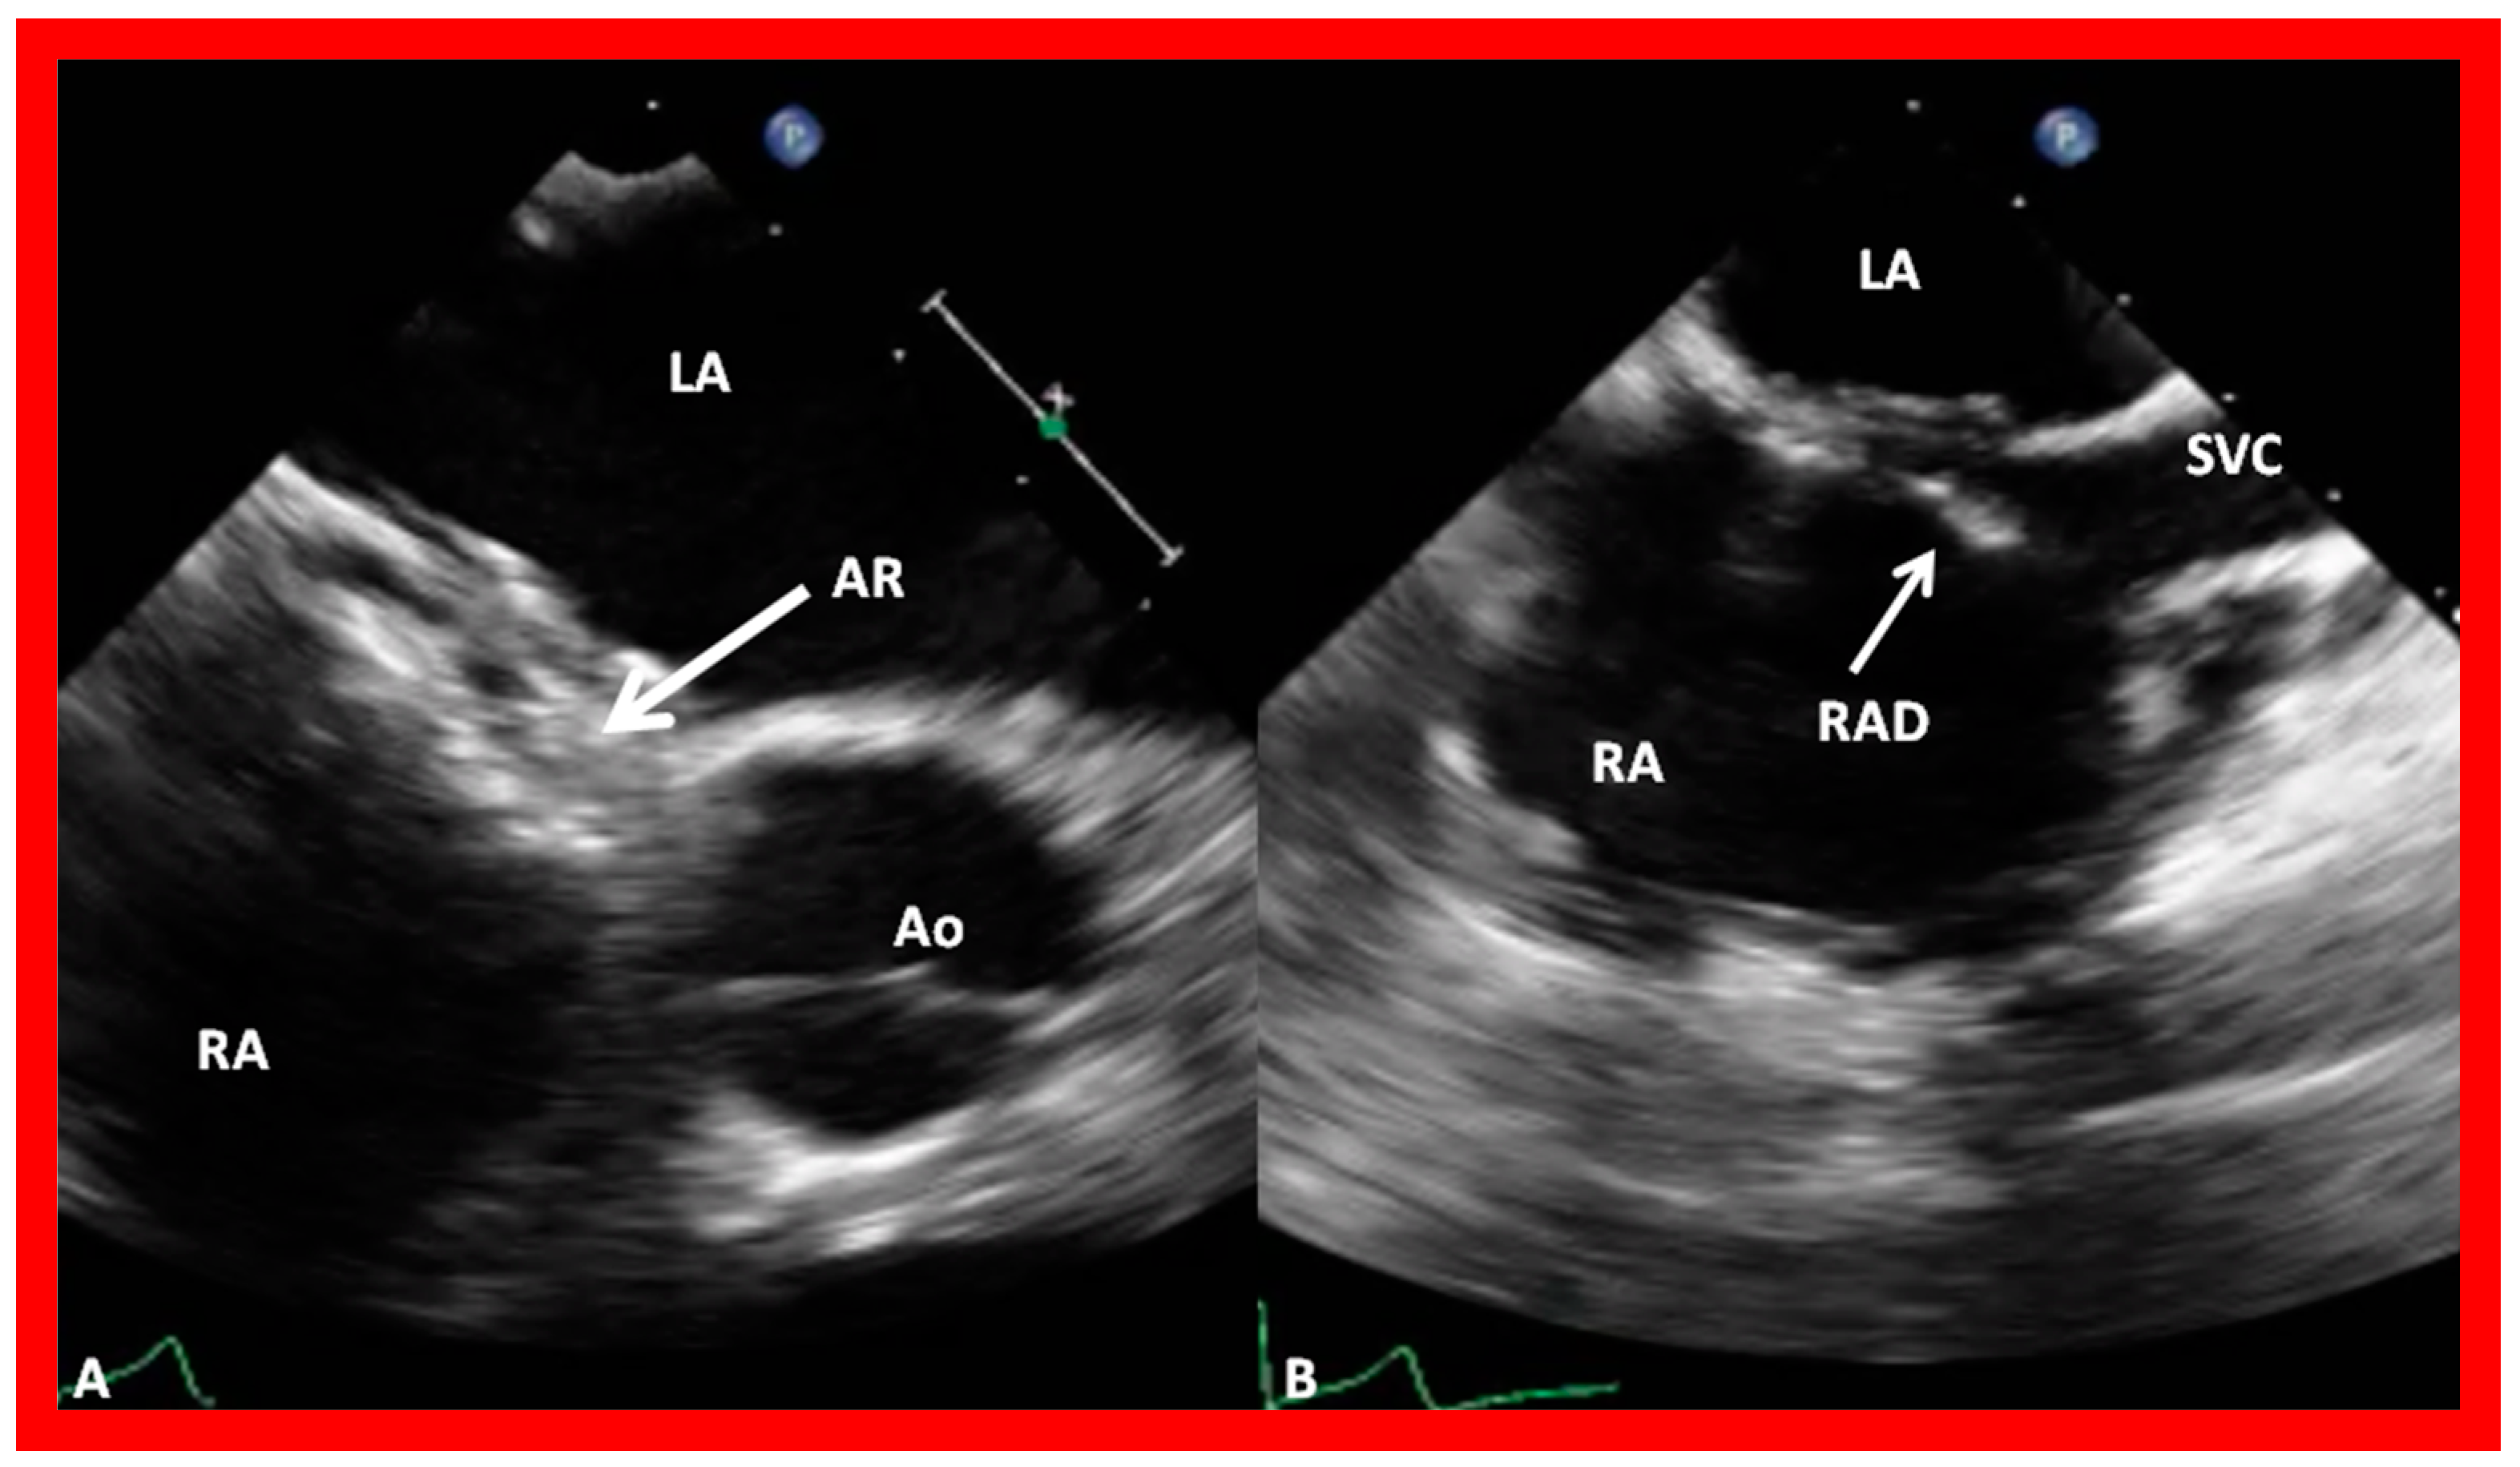

9.6. Obstruction of Systemic and Pulmonary Venous Drainage

9.7. Thrombus Formation

9.8. Device Migration